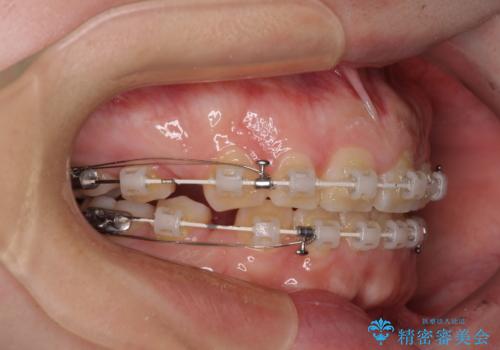

- 矯正装置

- 審美装置

- 出っ歯と口の閉じにくさ、デコボコを気にして来院された患者様です。

口元の突出感を改善するため、上下左右第一小臼歯4本の抜歯を行い、ワイヤー装置による矯正治療を行うこととしました。